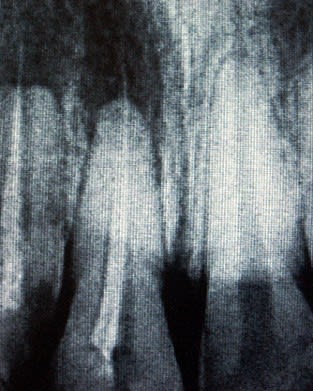

JH 22 ans vu en urgence pour douleurs de type abcès sur 11.

Sur la radio préop, les endos sont incomplètes et les cônes dépassent largement des apex sur 11 et 12 (pour moi c'est un massacre surtout sur une centrale).

P.S: on voit aussi une résorption des apex sur la radio préop par rapport à 21. Est ce forcément évolutif?